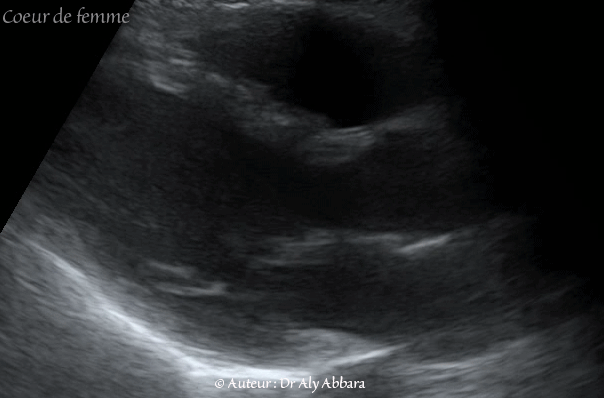

Echocardiographie - cœur d'une femme adulte - Continuité aorto-septale, aorto-mitrale - الإستمرارية التشريحية للإبهر مع الحاجز مابين البطيني ومع الصمام التاجي

Images échocardiographiques montrant, sur le cœur d'une femme adulte de 32 ans, l'aspect échographique de la continuité aorto-septale, aorto-mitrale.

Cette continuité aorto-septale et aorto-mitrale peut être observée sur le cœur fœtal.